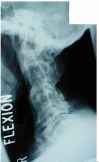

Case presentation: A 51-year male developed incomplete tetraplegia in 1997 when he slipped and fell backwards hitting his head on the floor. X-rays of cervical spine showed fusion at two levels: C2 and C3 vertebrae, and C4 and C5 vertebrae. Intravenous urography (IVU) revealed no kidneys in the renal fossa on both sides, but the presence of crossed, fused renal ectopia in the left ilio-lumbar region. This patient had a similar cervical spinal cord injury about 15 years ago, when he developed transient numbness and paresis of the lower limbs following a fall.